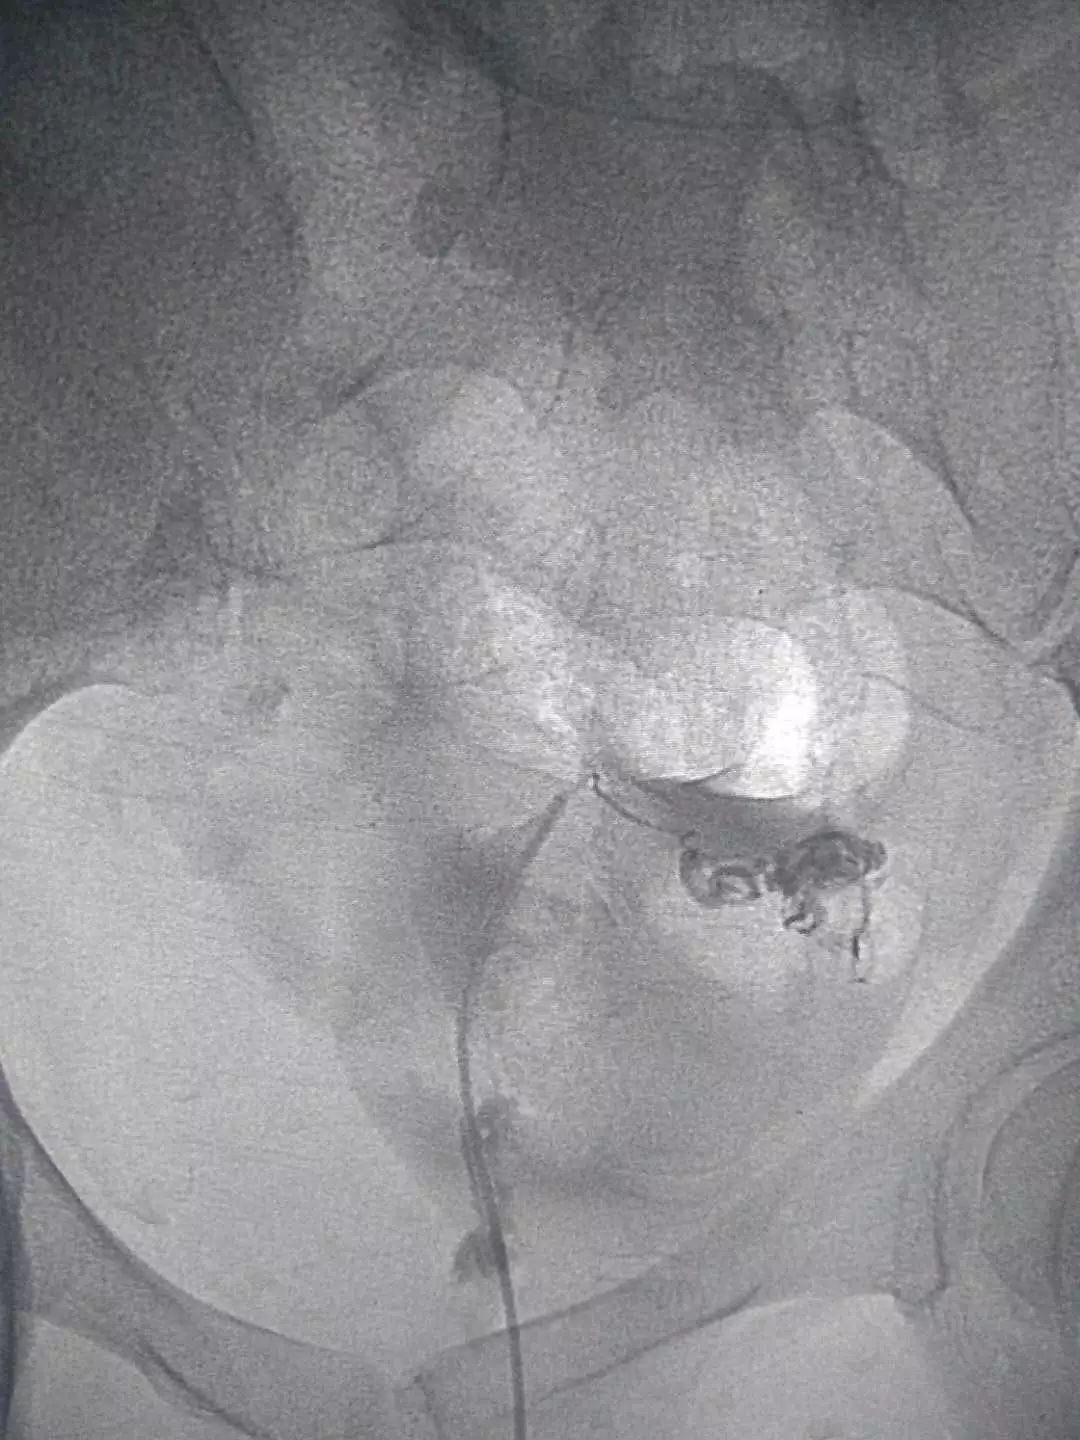

这是我院介入科开展的其中一例输卵管再通术:

患者四年前由于一次流产,之后一直不孕,在当地行子宫输卵管造影发现右侧有输卵管狭窄,当时采取保守治疗。四年来一直未孕。经过沟通,她在我院接受了输卵管介入复通术治疗。

造影视:双侧输卵管近段狭窄,右侧伞端通而不畅,左侧输卵管管壁不规则,通而不畅。

依次开通右侧输卵管+灌注药物,左侧输卵管+灌注药物,造影,显示左侧输卵管完全通畅。